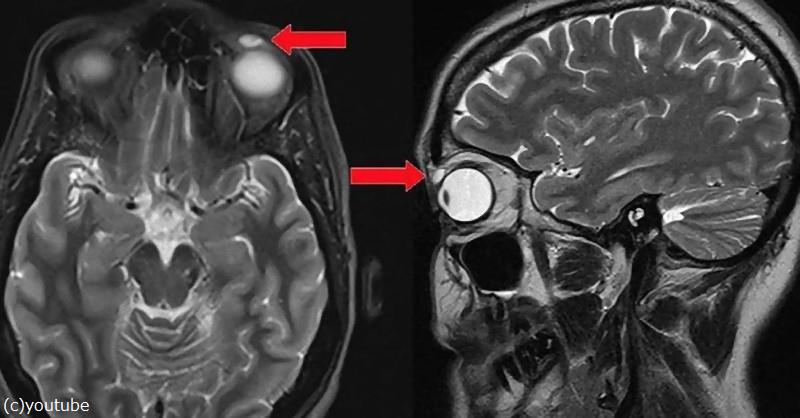

MRI検査をしてみたところ、まぶたの内側のあたりに何か異物が写っていたのです。

水泡から出てきたものは、ハードコンタクトレンズ。取り出す際に欠けましたが、発見時は完全な状態だったそうです。